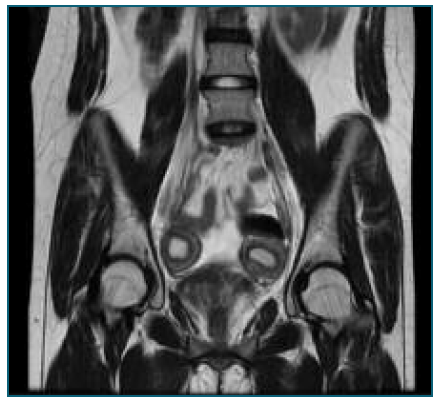

Figure 3 Left hemi-uterus and right functional rudimentary cavity (MRI).

2D and 3D transvaginal gynecologic ultrasound are the first-line imaging modalities to assess these women. However, MRI is a non-invasive exam, making it particularly useful in pediatric and virgin patients5 (Figure 3).